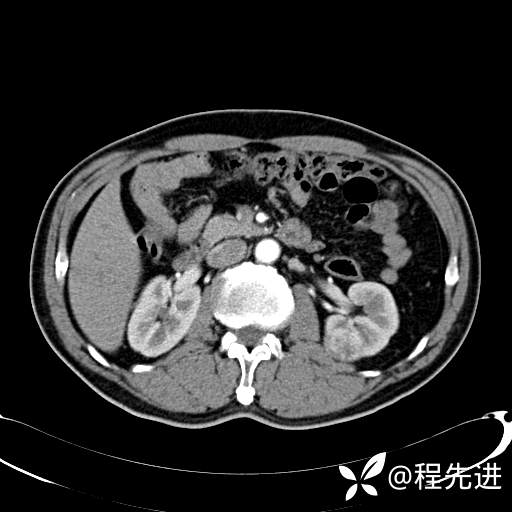

患者性别:男

患者年龄:65岁

简要病史:腰痛2月,体检发现左肾占位5天

排泄期:

肾透明细胞癌 (27)